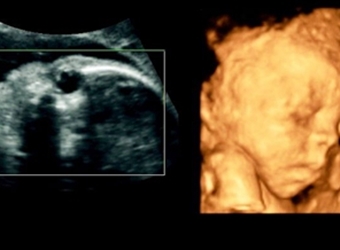

四维彩超是目前比较流行的孕检之一,四维能对胎儿头面部立体成像,可清晰显示胎儿的状态,网上很多四维是女孩但是却生了男孩的案例,那么四维女孩翻盘几率大吗…

四维彩超是实时的立体成像,在孕检的时候主要是帮助筛查胎儿的畸形,四维由于清晰度高也有用来判断胎儿男女,那么四维看是男孩有可能是女孩吗,四维男翻女的几…

四维彩超的报告中有很多的指标,网上也流传了很多通过报告单看男孩女孩的方法,那么四维胎儿双侧肾盂无分离是男是女,5个月四维如何看男女呢?更多关于生男生…

很多网上的宝妈都有看到这个情况,那就是做了四维彩超是男孩,但是却生了女孩,很多宝妈担心四维做的是男宝有可能翻盘吗,为什么四维男宝变女宝?更多关于生男…

网上有一种说法是,在做四维彩超的时候,如果是女宝宝是比较不容易配合的,如果是男宝宝更容易通过,那么是不是四维女宝更容易配合呢,四维女宝特征有哪些?更…

做四维彩超的时候,需要宝宝在肚子里动起来,有配合效果才是最好的,网上说做四维的时候不配合的都是女宝宝,那么这种说法是真的吗,四维是女宝还会翻盘吗?更…

很多宝妈都有在网上看到,做四维彩超的结果是女孩,但是最后生下的是男孩的案例,那么四维看是女孩最后会是男孩吗,女孩翻盘男孩的几率大不大?更多关于生男生…

网上流传着很多宝妈做四维彩超检查,医生说是男孩,但是结果生出来是女孩的案例,那么四维彩超男孩翻盘实例有哪些,为什么四维是男孩结果生女孩?更多关于生男…